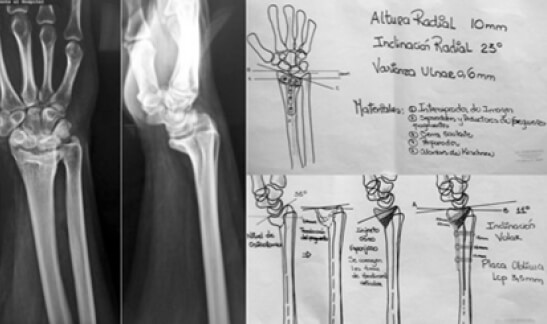

Una vez ingresado el paciente al protocolo, se le realizó una historia clínica y se aplicó el instrumento de recolección de datos para obtener las variables epidemiológicas. Para la planificación preoperatoria se solicitaron radiografías anteroposterior y lateral de muñeca afectada y contralateral sana, así como TC de muñeca con reconstrucción 3D, se realizó la planificación pre-operatoria correspondientes con calcos para la determinación del Centro de Rotación de la Angulación (CORA) de la deformidad y así establecer el nivel de corte de la osteotomía (Ver figura 1).

Figura 1. Técnica Quirúrgica: Planificación pre-operatoria.

La técnica quirúrgica se basó en la realización de osteotomía correctora intraarticular o extra articular, a través de un abordaje volar con un promedio de tiempo de la intervención de 2 a 3 horas (Ver figura 2).